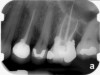

Fig 4. Preoperative radiograph showing aggressive external root resorption and thin dentinal walls.

Figure 4

Clinical procedure: Regeneration of the endodontic pulp space is indicated for cases with very thin dentinal walls and an open apex that is more than 1 mm in diameter radiographically (Figure 4). Disinfection of the root canal system is performed using sodium hypochlorite irrigation followed by a triple antibiotic paste dressing that is left in place for 1 week. At the second visit, ethylenediaminetetraacetic acid (EDTA) is used to condition the dentin walls, which results in the release of growth factors, and bleeding is stimulated in the periapical tissues (where stem cells are located), with the aim of filling the pulp space with a stable blood clot, which would serve as the scaffold. MTA is then placed at the canal orifice in contact with the clot to protect it from coronal microleakage (Figure 5 and Figure 6). In time, the clot should be replaced with a reparative tissue of variable composition, and the root walls should continue to thicken due to the deposition of a dentin-like material on the pre-existing root dentin27,28 (Figure 7 and Figure 8).